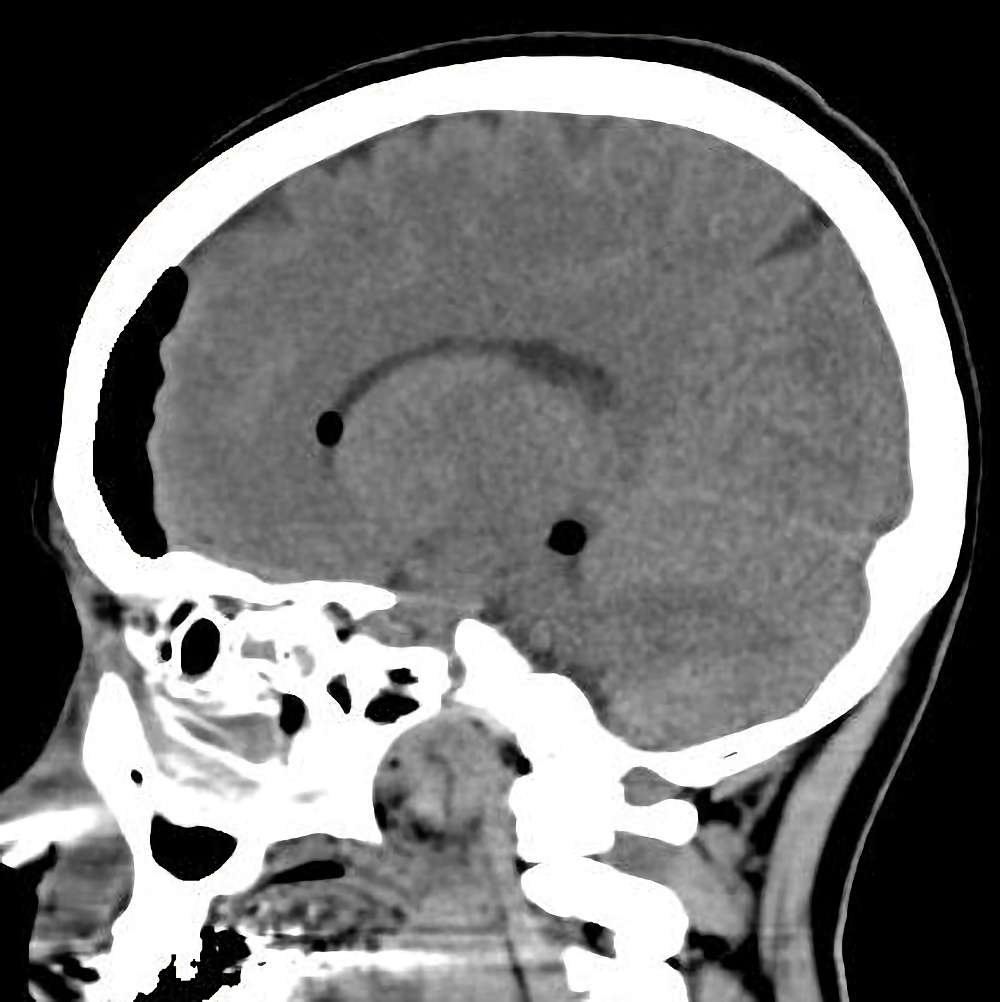

頭蓋咽頭腫

手術前1

No.’13_130 手術前1